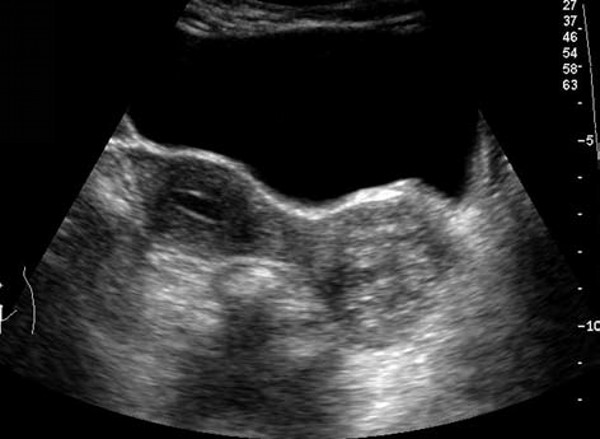

患者,女,28岁。因接触性不规则阴道流血3个月来院就诊。超声检查报告显示宫颈增大,形态不规则,有一6.0 cm×4.5cm×5.1cm低回声区,境界不清,回声分布不均匀。CDFI:见稀疏血流。

超声提示:宫颈实质性占位病变(符合宫颈癌)。

病理诊断:子宫颈大细胞非角化性鳞形细胞癌,浸润宫颈壁全层。